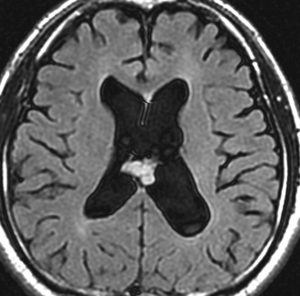

10年観察してもあまり変わらない,数が増えることがある

2012年に偶然発見され,その後,10年の経過観察されました。

2022年のものです,透明中核から出たものは少し大きくなっています。他にも数個の小さな腫瘍が脳室上壁にあるのですが,なにもしないでほっておきます。